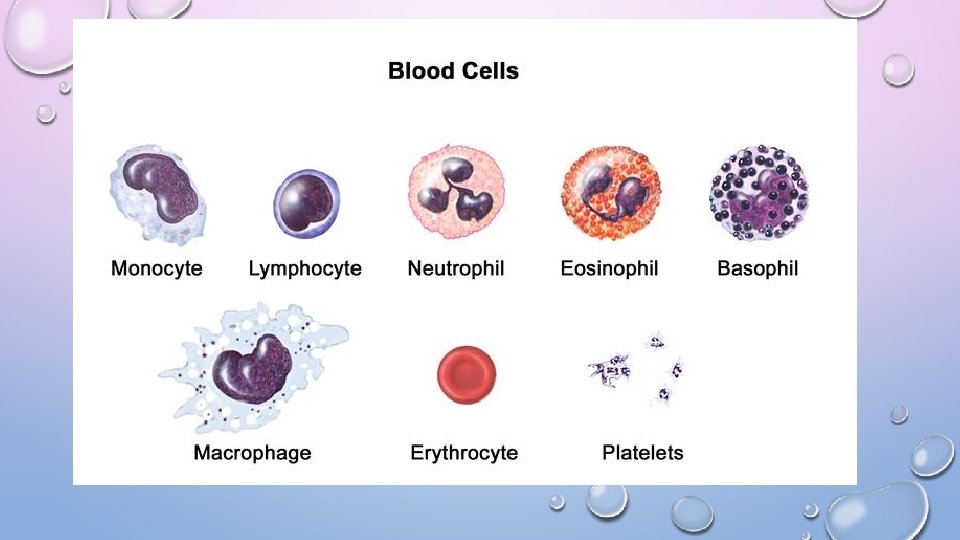

BLOOD COMPONENTS 2. ERYTHROCYTES- AKA RED BLOOD CELL • CARRY HEMOGLOBIN, • NO NUCLEUS, 120 DAY LIFE, • CANNOT REPAIR THEMSELVES, ERYTHROPOIESIS

3. LEUKOCYTES- WHITE BLOOD CELLS FORMED IN BONE MARROW, FIGHT INFECTION 5 TYPES • NEUTROPHIL - 58%; MAIN DEFENSE, PHAGOCYTOSIS • LYMPHOCYTE- 30%; B AND T CELLS, IMMUNITY, RECOGNITION • EOSINOPHIL- 2%; PARASITE/ALLERGIES • GRANULOCYTE- DIGESTIVE ENZYME

3. LEUKOCYTES- WBC 5 TYPES (CONTINUED) • BASOPHIL- 1%, ALLERGIES? ? ? UNKNOWN • GRANULOCYTE • MONOCYTE- 4% CREEPERS • GO AND LIVE IN TISSUES AND COME OUT WHEN NEEDED • GRANULOCYTE

CLOT IT UP! • 4. THROMBOCYTES- PLATELETS • CLOT BLOOD BY STICKING TOGETHER AND SECRETING PROTEIN CALLED FIBRIN • SUPER SMALL